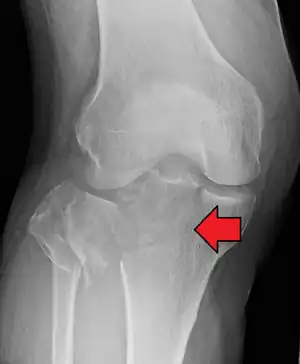

Subtle tibial plateau fracture on an AP X ray of the knee -

A tibial plateau fracture seen on X-ray